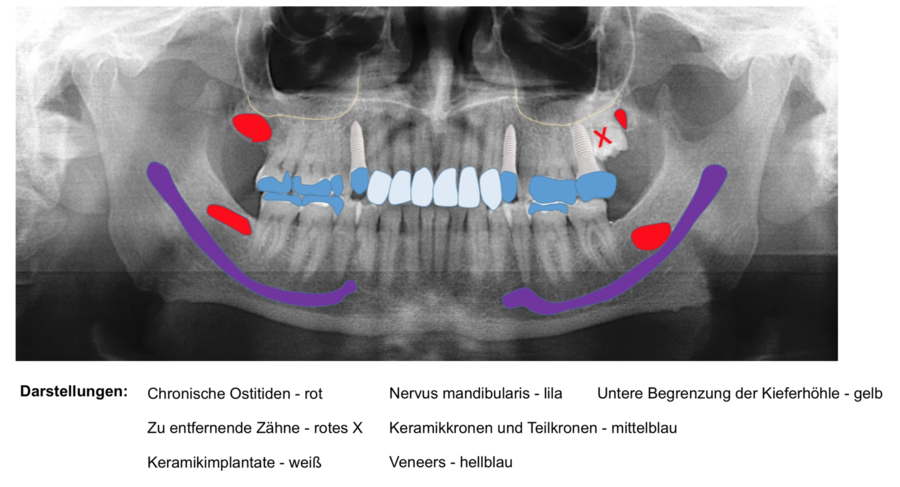

Hinweis: Sollten Sie bereits über eine aktuelle Panoramaschichtaufnahme verfügen, können Sie diese gerne vorab per E-Mail an uns schicken (info@biologische-zahnmedizin-kiel.de). Wenn es kein aktuelles Röntgenbild gibt, erstellen wir es vor Ort für Sie.